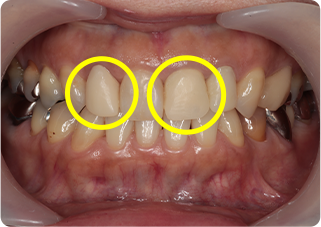

セラミッククラウン症例②

術前

仮歯

術後

| 主訴 | 前歯を綺麗にしたい、隙間が気になる |

| 治療期間/回数 | 4ヵ月、6回 |

| 価格(税込) | 792,000円(税込) |

| リスク・副作用 | セラミック破損の可能性 |

| ポイント | 仮歯で歯ぐきの状態を整え、自然な色、形となるようにオーダーメイドでセラミックを盛り、クラウンを作製した。 |